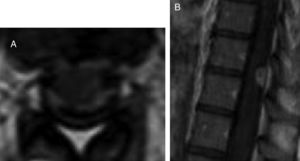

We present the case of a 23-year-old immunocompetent Berber woman who, after a second caesarean section with epidural anaesthesia, presented headache, neck rigidity, and subacute nausea progressing for 2 weeks; fever was not observed. A brain computed tomography scan showed normal findings, but a subsequent lumbar puncture revealed thick cerebrospinal fluid with low glucose levels, lymphocytic pleocytosis, and elevated adenosine deaminase (ADA) activity. A chest radiography revealed no abnormalities. Several hours after starting empirical treatment with tuberculostatic drugs (isoniazid 300 mg + pyrazinamide 1600 mg + rifampicin 600 mg + ethambutol 1100 mg/day, orally) and steroids (dexamethasone 4 mg/8 h), the patient presented neurological impairment with confusional symptoms, paraparesis of the lower limbs and anaesthesia from T10, and urinary retention. Neuroaxial magnetic resonance imaging (MRI) revealed communicating hydrocephalus, brain and spinal meningeal enhancement, posterior fossa tuberculomas, and a spinal extra-axial contrast-enhanced lesion at the T10 level suggestive of epidural abscess (Figs. 1 and 2). We observed no vertebral involvement. The Löwenstein-Jensen medium yielded positive results for Mycobacterium tuberculosis.